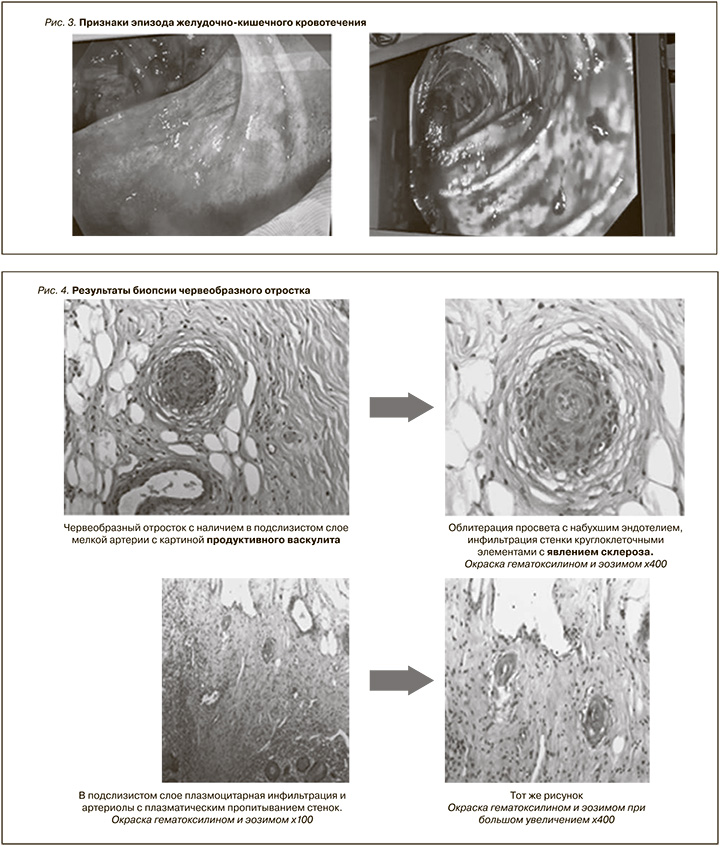

На 26-е сутки нахождения в стационаре отмечено развитие второго эпизода желудочно-кишечного кровотечения, потребовавшего проведения оперативного вмешательства в объеме лапароскопической аппендэктомии (рис. 3).

По результатам полученной биопсии удаленного аппендикса были выявлены признаки продуктивного васкулита с микротромбозами в стенке (рис. 4).